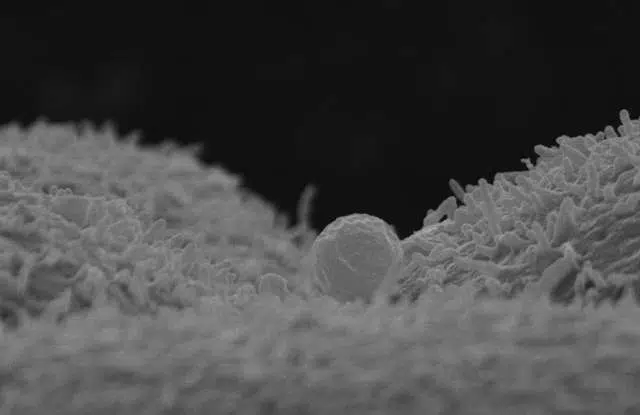

Un estudio de la Fundación IVI (FIVI) titulado Hsa-miR-30-d, secreted by the human endometrium, is taken up by the pre-implantation embryo and might modify its transcriptome, publicado en la revista científica Development, por los investigadores de IVI, Felipe Vilella y Carlos Simón -director científico FIVI-, demuestra por primera vez en la historia de la genética, algo que ya propuso Barker en 1990 cuando dijo que “lo que sucede en el útero materno es más importante que lo que sucede en la casa tras el nacimiento”: la comunicación entre gestante y embrión, dando lugar a modificaciones en el genoma del futuro bebé.

Este trabajo demuestra que la madre puede modificar la información genética del hijo, aun cuando el óvulo es de una donante o entre gestante subrogada y bebé, lo que cambia por completo el paradigma de la ovodonación y subrogación de útero, abriendo la puerta a la esperanza de aquellas madres que tienen que recurrir a la donación ovocitaria para cumplir sus deseos reproductivos y alertando a aquellas que optan por una subrogación, sobre la importancia de la madre de sustitución y la información que emana.

“Este hallazgo nos muestra que existe un intercambio entre endometrio y embrión, algo que ya sospechábamos por la coincidencia de algunos rasgos físicos entre madres e hijos de ovodonación así como por la incidencia de enfermedades de los niños relacionados con patologías maternas durante la gestación como obesidad o tabaquismo”, explica el investigador Felipe Vilella.

Determinadas condiciones a las que se someten las mujeres acaban modificando sus células (también las del endometrio): el tabaquismo o la obesidad, lo hacen. Esto produce que el líquido endometrial cambie también y en su secreción, se encuentre la liberación de información genética de la gestante que es tomada por el embrión, modificando así su desarrollo.

“Esta comunicación puede inducir a que en el embrión se expresen o se inhiban funciones específicas dándose lugar a modificaciones que nos muestra el proceso de transmisión de enfermedades como la Diabetes o la Obesidad”, han explicado los investigadores, “así pues esta publicación abre la puerta a poder evitar este tipo de enfermedades cuando su causa es epigenética. Sabiendo que existe esta transmisión, en el futuro podremos detectar cómo cortarla acabando con la tónica de madres obesas, hijos obesos o en los países en los que se permite la subrogación de útero, darle más importancia al historial de hábitos previos a la gestación, de la gestante.